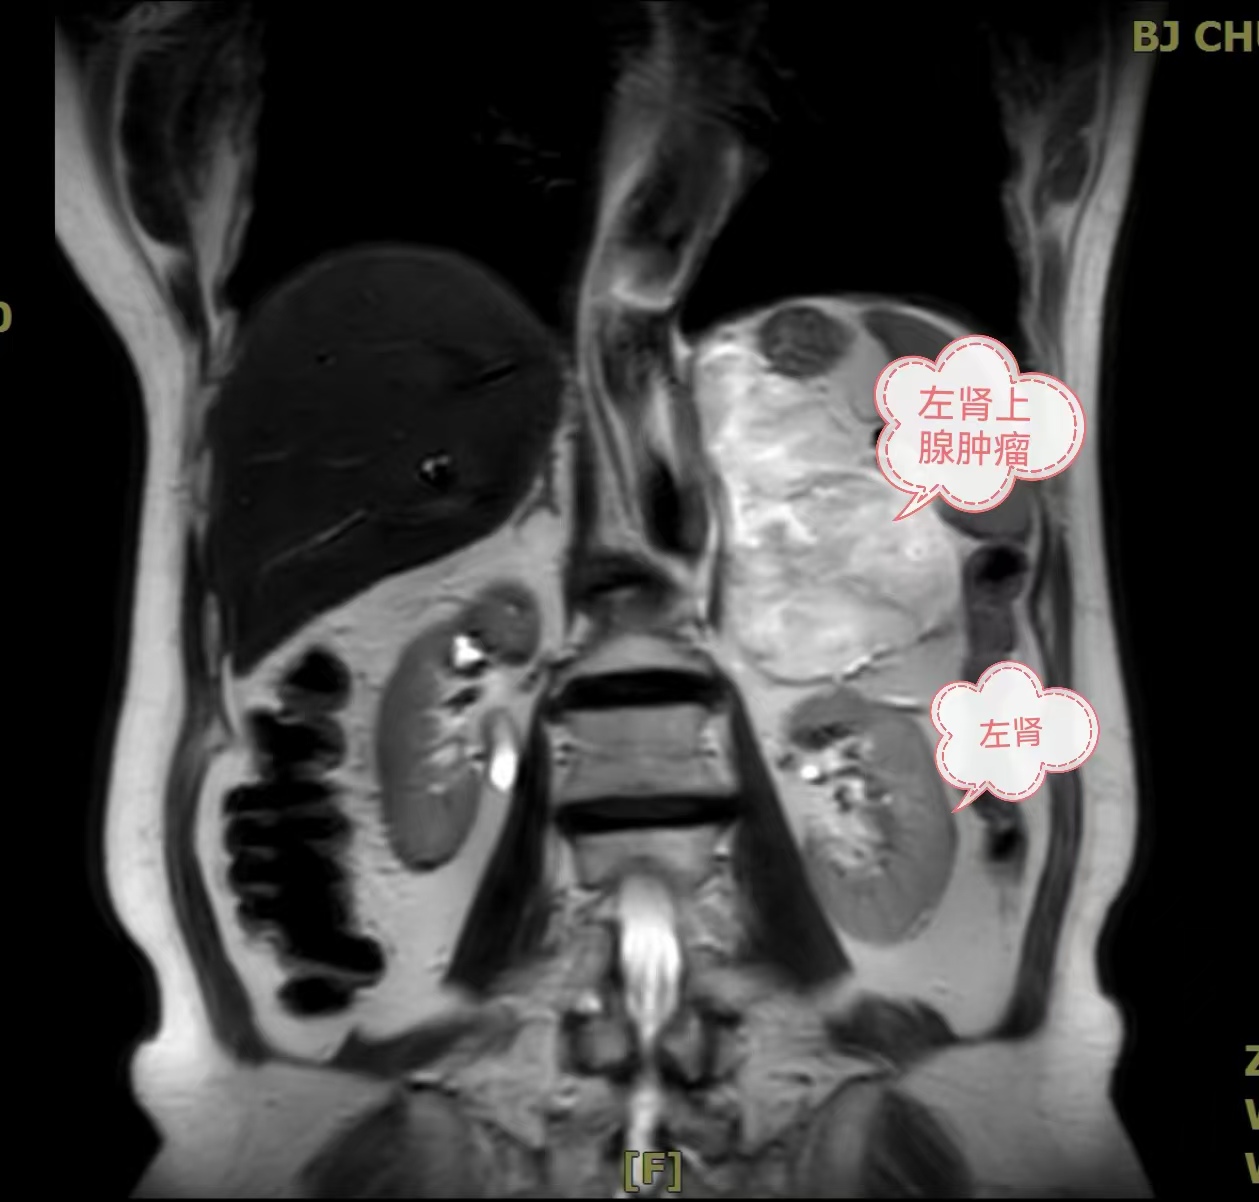

在现代医疗技术的辅助下,北京市垂杨柳医院泌尿外科团队近日完成了一项高难度的微创手术。一位72岁女性患者在医院泌尿外科接受了腹腔镜下的左侧肾上腺巨大肿瘤切除术。患者肿瘤直径达到惊人的13厘米,整个手术过程仅用时1小时,出血量控制在约30毫升,体现了医院泌尿外科在腹腔镜手术领域的专业实力和对患者痛苦的深切关怀。

肾上腺肿瘤是泌尿系统较为常见的疾病之一,而直径超过8厘米的肾上腺肿瘤通常需要通过开放手术来治疗。然而,传统的开放手术往往伴随着较大的创伤和较长的恢复时间。为了最大程度地减轻患者的疼痛与不适,同时确保手术的安全性和有效性,泌尿外科首席专家谷现恩和科主任龙建华带领团队在充分评估后决定采用腹腔镜技术进行手术。